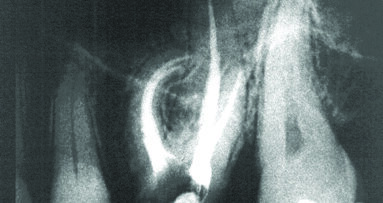

Kako izveštava internet portal MailOnline, prvi korak u ovom novom endodontskom tretmanu bila bi aplikacija antibiotske paste u cilju dezinfekcije inficirane zubne pulpe, dok bi u drugoj poseti nakon petnaest dana specijalnim instrumentom stomatolog napravio male rezove u kanalima korena zuba koji treba da izazovu krvarenje koje bi dovelo do stvaranja krvnog ugruška. Istraživanje je pokazalo da ovaj novostvoreni krvni ugrušak dovodi do stvaranja novih krvnih sudova, što povećava količinu kiseonika i hranljivih materija u kanalu korena zuba i time podstiče reparaciju oštećene zubne pulpe. Iako mehanizam koji dovodi do ove reparacije zubne pulpe nije potpuno razjašnjen, pretpostavlja se da je osnovni razlog prisustvo faktora rasta u krvnom ugrušku, koji podstiče obnovu oštećenog tkiva zubne pulpe.